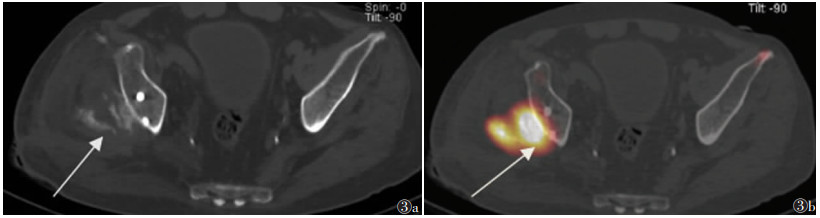

中期病变23例,X线(23例)、CT(16例)、MRI(12例)及SPECT/CT(4例)阳性率均为100.0%。X线或CT表现为软组织肿块周边高密度骨化影,14例呈絮状、片状或点状(图 1,2a,3a),9例呈蛋壳样骨化,肿块中央密度较低(图 4)。MRI示肿块呈分层状改变,最外侧(外层)呈条带状T1WI高信号、T2WI低信号(骨化);中间区(中间层)T1WI呈等信号、T2WI呈高信号;中心区域(内层)T1WI、T2WI均呈高信号;肿块外围呈边界不清的T2WI和STIR脂肪抑制高信号(水肿)(图 2b,2c)。SPECT/CT表现为病灶整体显像剂摄取,病灶中央摄取程度高于周围(图 3b)。

| 图 3 男,56岁,右侧髋关节骨化性肌炎(中期) 图 3a CT横轴位扫描图像,显示右侧髋臼后侧软组织内絮状、片状骨化影(箭头) 图 3b SPECT/CT横轴位融合图像,显示病灶区整体显像剂异常摄取,中央摄取程度高于周围(箭头) |

3.2 中期外伤后5~8周,病理上出现骨化,从病灶外周向中央发展,呈蛋壳样表现,可呈典型的3层表现,但较少见;临床表现为发热、局部肿块及压痛;影像表现为肿块周围逐渐出现骨化。本研究中此期患者X线、CT、MRI及SPECT/CT显像均为阳性。有研究[9]显示蛋壳样骨化是其特征影像表现,但本研究仅39.1%(9/23)出现此特征。MRI可呈典型3层表现,外层为骨化层,中间为萎缩肌纤维层,内层为出血层。关于核医学在骨化性肌炎的应用报道,多为个案报道,且病例均为中期,病灶显像剂异常摄取[10-13]。本研究中期骨化性肌炎SPECT/CT表现为病灶整体显像剂摄取,病灶中央摄取程度高于周围,提示骨化性肌炎是一种渐进的成骨过程,且从周围向中央进展。